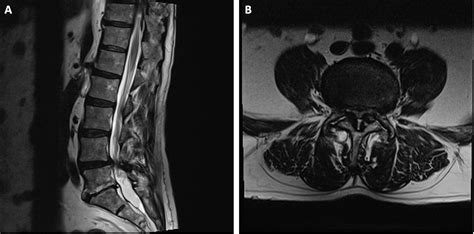

The human spine is a complex column of bones called vertebrae, cushioned by intervertebral discs and held together by ligaments and muscles. Spondylolisthesis is categorized by the degree of slippage. In a Grade 1 Spondylolisthesis, the instability is at its lowest clinical stage. This slippage most commonly occurs in the lumbar spine—the lower back—specifically at the L4-L5 or L5-S1 levels, where the stress on the spine is greatest due to weight-bearing activities.